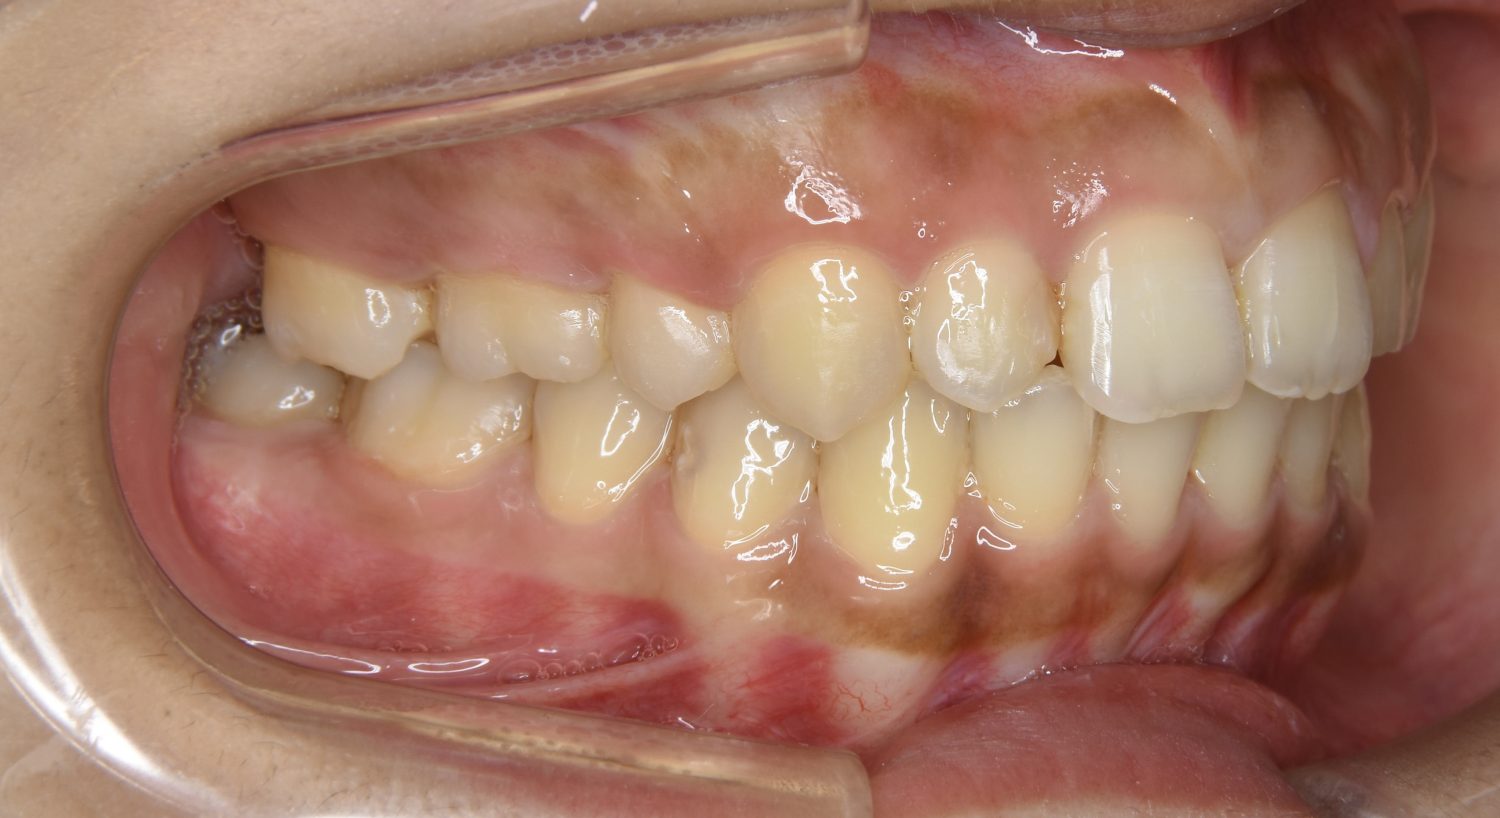

叢生の症例紹介②

Before

After

主訴

歯の凸凹を治したい。

治療内容

アライナー(インビザライン)にて非抜歯で治療を行いました。

治療費

1,150,000 円(税込)

治療期間

26ヶ月

通院回数

14回

想定されたリスク

※歯根吸収、歯肉退縮、歯髄壊死、顎関節症状

※アライナー(インビザライン)は日本の薬機法未承認の矯正装置であり、医薬品副作用被害救済制度の対象外となる場合があります。

丸山和宏先生

ピーススマイル矯正歯科

上下前歯部に叢生(凸凹)が認められる状態でした。歯列の遠心移動を行うことで機能面および審美面が改善されました。